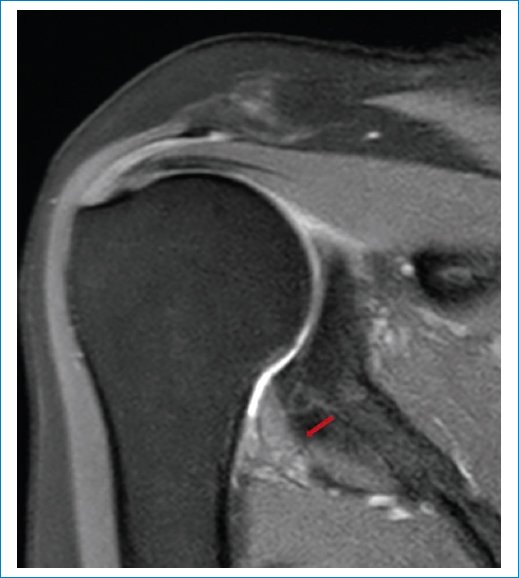

En nuestra serie aplicamos los criterios de Emig et al.11, que incluyen la hiperintensidad o el engrosamiento del ligamento glenohumeral inferior > 3 mm (Figs. 1 a 3), el engrosamiento capsular del receso axilar (con valores que varían según los estudios, pero descrito en general como > 7 mm) (Fig. 3), el engrosamiento del ligamento coracohumeral > 4 mm (Fig. 4), la infiltración grasa y la hiperintensidad del intervalo rotador (Figs. 5 a 7), y la obliteración de la grasa subcoracoidea (descrita como ausente, parcial o completa) (Fig. 8).

Figura 8. RM en secuencia potenciada en T2, corte sagital. Se observa obliteración de la grasa subcoracoidea (asterisco).